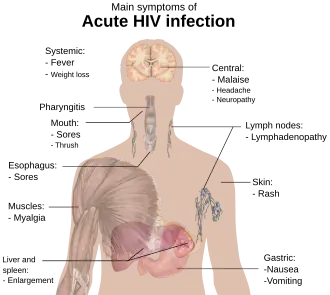

HIV is the same as AIDS

HIV is an acronym for human immunodeficiency virus, which is the virus that causes AIDS (acquired immunodeficiency syndrome). Contracting HIV can lead to the development of AIDS or stage 3 HIV, which causes serious damage to the immune system. While this virus is the underlying cause of AIDS,[3] not all HIV-positive individuals have AIDS, as HIV can remain in a latent state for many years. If undiagnosed or left untreated, HIV usually progresses to AIDS, defined as possessing a CD4+ lymphocyte count under 200 cells/μL or HIV infection plus co-infection with an AIDS-defining opportunistic infection. HIV cannot be cured, but it can be treated, and its transmission can be halted. Treating HIV can prevent new infections, which is the key to ultimately defeating AIDS.[4]

HIV-positive individuals can be detected by their appearance

Due to media images of the effects of AIDS, many people believe that individuals infected with HIV always appear a certain way, or at least appear different from an uninfected, healthy person. In fact, disease progression can occur over a long period of time before the onset of symptoms, and as such, HIV infections cannot be detected based on appearance.[26]